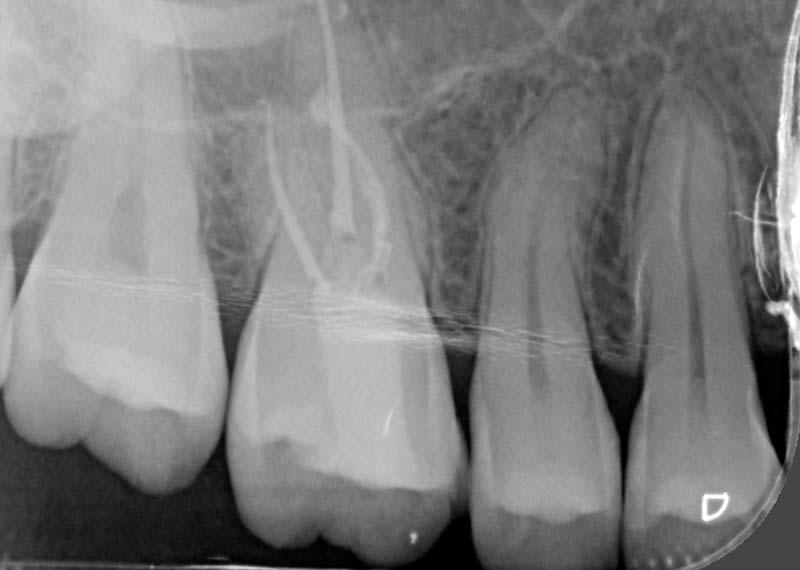

We use a digital intraoral scan to capture a detailed 3D image of your teeth and gums in real time. This helps us detect hidden issues such as cracks, gum problems, or early decay that may be causing your toothache.

Sometimes the problem goes deeper than what we can see. When bacteria reach the inner nerve of the tooth, it can cause persistent pain or infection.

A root canal treatment (RCT) aims to remove the infection, relieves your pain, and saves your teeth.

For: Compromised pulp (decay or cracked tooth)